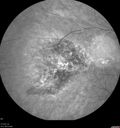

64 year old man. Diagnosed with hemangioma in 2015. PDT in 2016. Images are from 2020 when fluid started to reaccumulate. Needed PDT repeated two more times. PDT treatments: [1] 2/19/2015 -  Pavan (IOP  problem after PDT)  AND [2] 11/2/21 PDT (7 mm temporal to fovea) - SMC  AND [3] 7/22/22 PDT 7.5 mm Temporal to the fovea

Choroidal Hemangioma Requiring PDT repeatedly199 views64 year old man. Diagnosed with hemangioma in 2015. PDT in 2016. Images are from 2020 when fluid started to reaccumulate. Needed PDT repeated two more times.

PDT treatments: [1] 2/19/2015 -  Pavan (IOP  problem after PDT)  AND [2] 11/2/21 PDT (7 mm temporal to fovea) - SMC  AND [3] 7/22/22 PDT 7.5 mm Temporal to the fovea